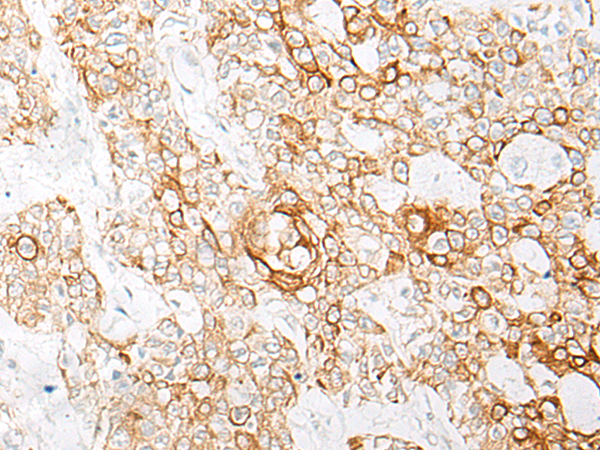

IHC positive control: |

Human esophagus cancer; Human prostate cancer |